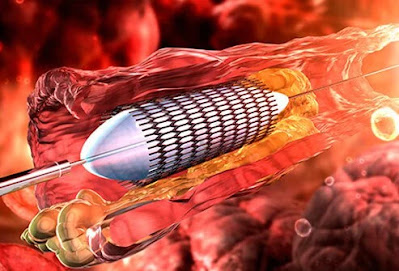

Θεραπεία καρδιακών παθήσεων: Αγγειοπλαστική

Η αγγειοπλαστική μπορεί να βοηθήσει στην πρόληψη καρδιακών προσβολών ανοίγοντας φραγμένες στεφανιαίες αρτηρίες.

Άλλες θεραπείες για καρδιακές παθήσεις περιλαμβάνουν ειδικές τεχνικές όπως αγγειοπλαστική και τοποθέτηση stent.

Αγγειοπλαστική Βήμα προς Βήμα

Ένας λεπτός καθετήρας ή σωλήνας (στεντ) τοποθετείται σε στεφανιαία αρτηρία και περνά με σπείρωμα μέσω απόφραξης σαν θρόμβος.

Ένα μπαλόνι είναι φουσκωμένο και παραμερίζει το εμπόδιο.

Το μπαλόνι στη συνέχεια ξεφουσκώνει αφήνοντας την αρτηρία ξεμπλοκαρισμένη, επιτρέποντας έτσι καλή ροή αίματος.

Συχνά, μετά από αγγειοπλαστική, ένας διαστελλόμενος σωλήνας πλέγματος εισάγεται και επεκτείνεται, ενισχύοντας την αρτηρία για να μην καταρρεύσει.